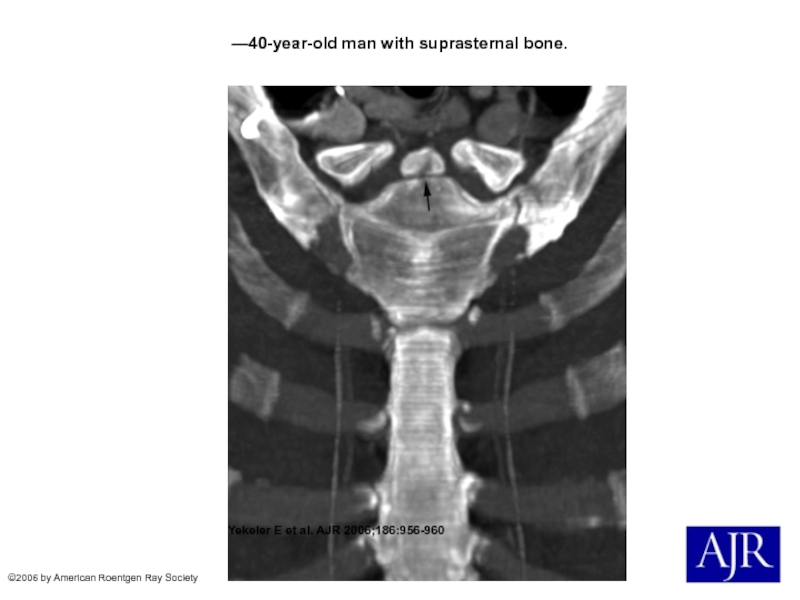

Слайд 17—40-year-old man with suprasternal bone.

Yekeler E et al. AJR

2006;186:956-960

©2006 by American Roentgen Ray Society

—40-year-old man with suprasternal bone. Yekeler E et al. AJR 2006;186:956-960©2006 by American Roentgen Ray Society